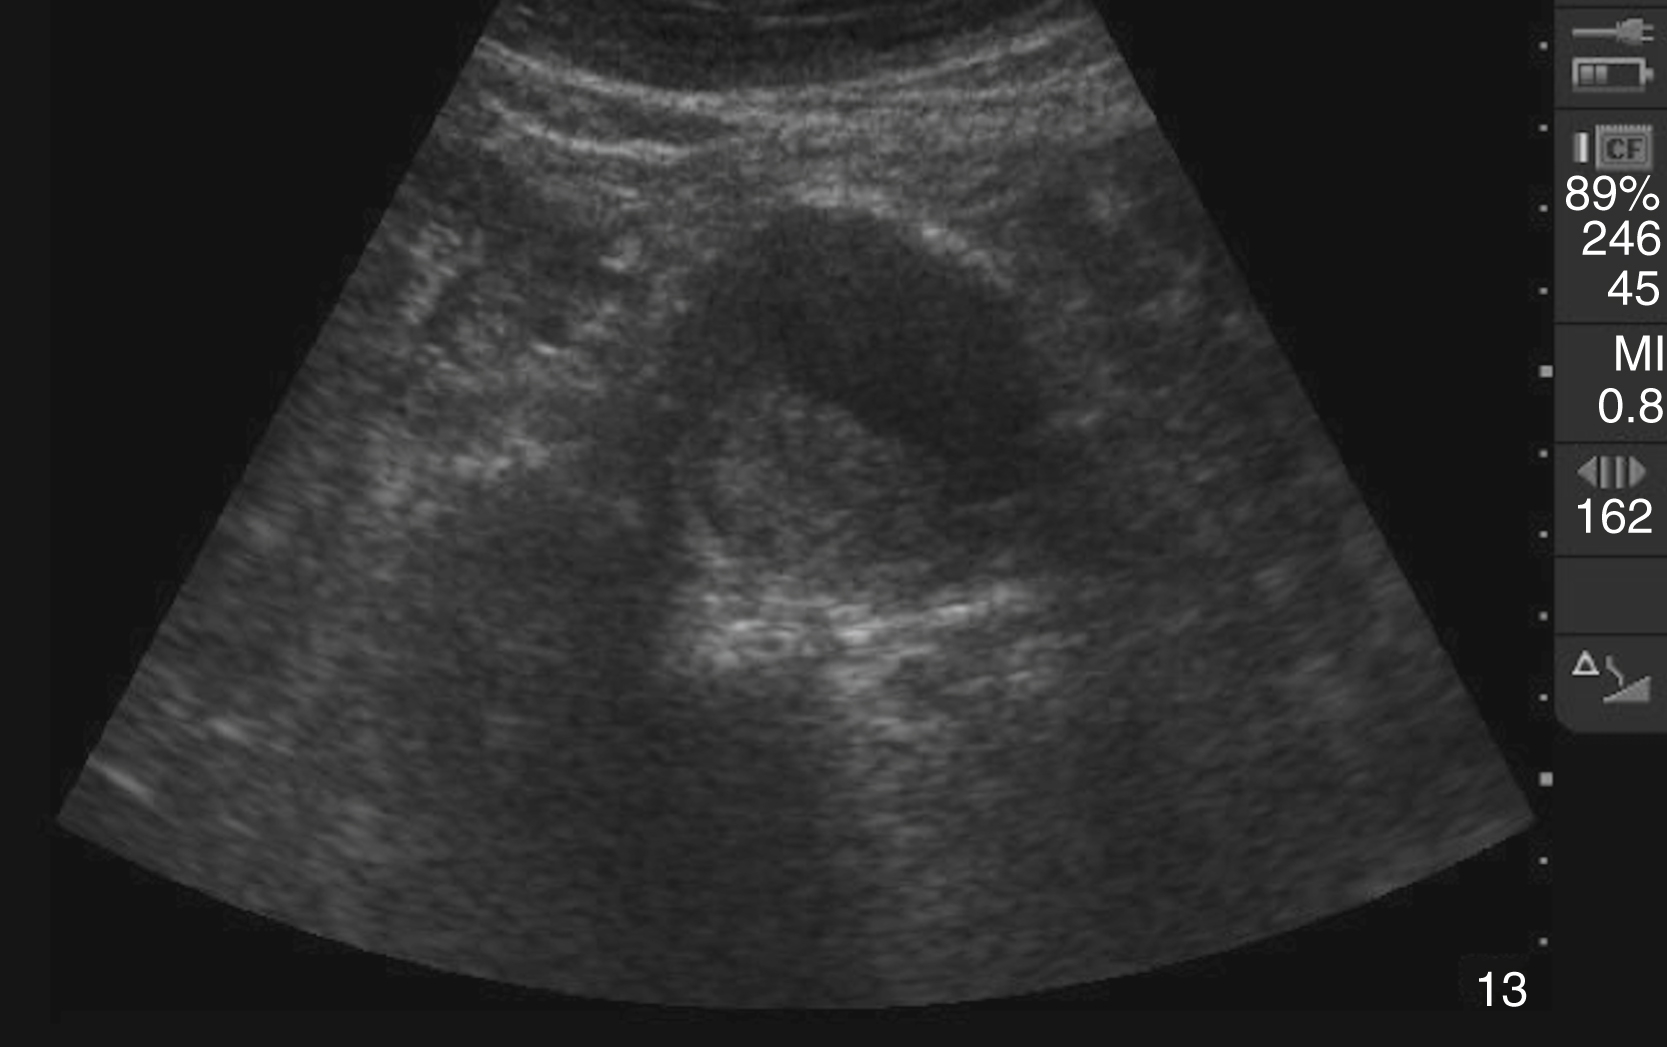

Hydronephrosis is characterized by dilation and anechoic fluid accumulation within the renal pelvis and calyces, ranging from mild to severe ( Fig. e3.6 ). Renal and/or ureteral calculi may be identified as echogenic foci with associated shadowing and are usually located within the kidney (nonobstructive) or in the renal pelvis, proximal ureter, or uretero-vesicular junction. Color Doppler placed over the kidney can help differentiate mild hydronephrosis from the renal vasculature, as well as possibly accentuate any renal stones by producing the renal twinkle artifact.

Hydronephrosis with dilation of the calyces and renal pelvis of the kidney showing thinning of the cortex, signifying severe hydronephrosis.